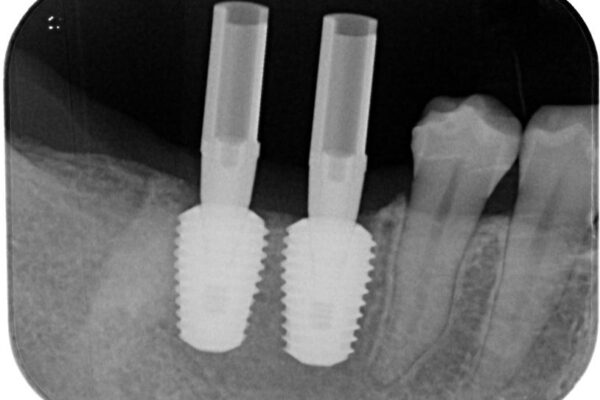

スペースが整った段階で、右下の第一大臼歯と第二大臼歯にインプラントを埋入。

• 挺出歯を圧下してスペースを確保!目立たない部分矯正で下顎大臼歯にインプラント治療を実現 治療途中画像